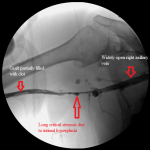

- Line diagram illustrating the findings of and interventions.

They belong to a patient whose graft failed the day after his last hemodialysis. The line diagram is a composite illustration of the anatomy of the graft, the deep veins of the upper right arm, the central veins, observations I made during the intervention, and the materials I employed in the treatment.

The graft is a straight polytetrafluoroethylene graft anastomosed to the distal right brachial artery and the mid right brachial vein. It had neither pulse nor thrill on clinical examination, suggesting it was thrombosed. There were multiple dilated veins on the patient’s upper right chest indicating central venous stenosis.